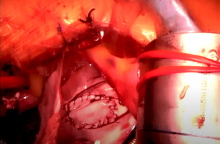

Minimally Invasive ASD Repair: Step-by-Step Guide [1]

Atrial septal defect (ASD) is one of the most common congenital lesions in adults. Percutaneous device closure remains the preferred approach. For ASDs that are not amenable to percutaneous closure, minimally invasive ASD repair represents an important and safe alternative.